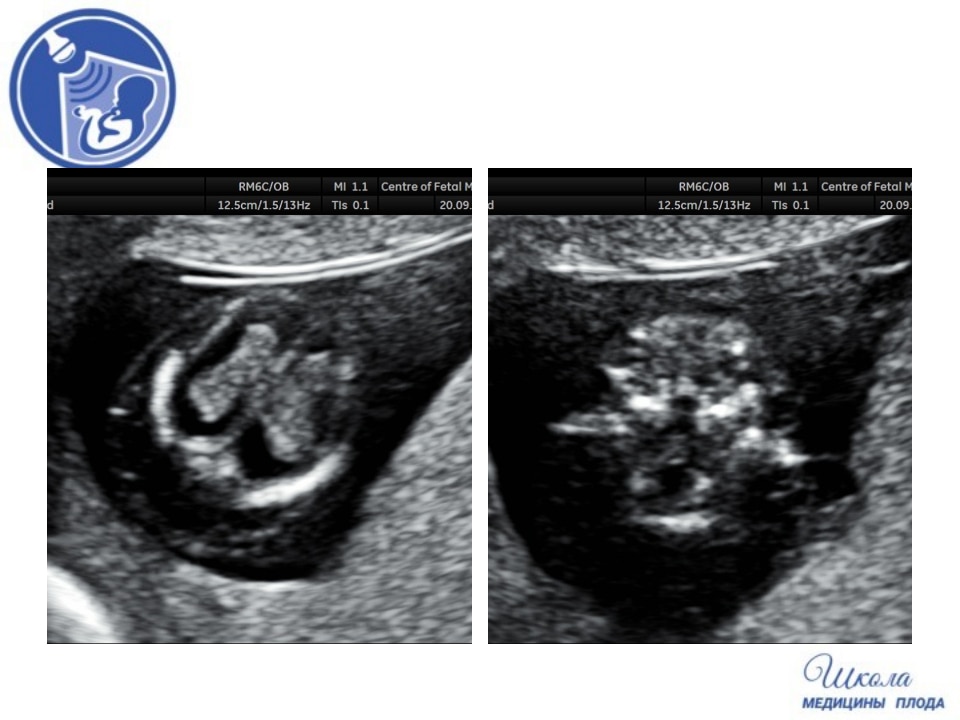

Вопрос 2

Пациентка пришла на УЗИ при сроке 12 недель 5 дней. Проанализируйте изображения и клип сердца и дайте свое заключение